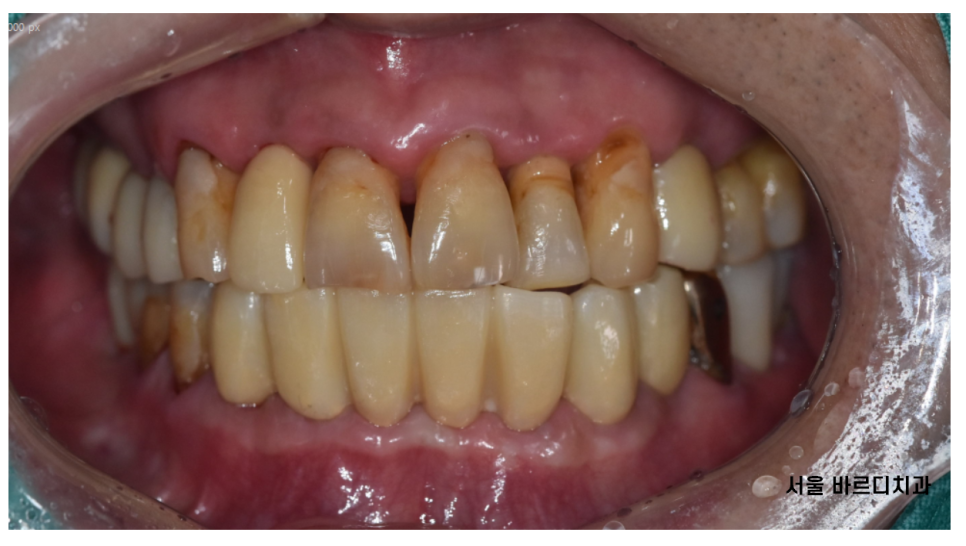

구강 내 사진을 보시면

전반적으로 치아가 길어보이죠~?

주황색 라인까지 잇몸이 덮여 있어야하는데

잇몸뼈가 내려가면서

치아도 길어져 보이는거죠~

치아 뿌리 부분만 붙잡고 있으니

위아래 치아 흔들림과 함께

통증이 있었습니다.

240724

임플란트로 치료해드렸지만

똑같이 관리가 안될 경우

임플란트를 제거해야할 수도 있음을

강조해드렸습니다.

3개월 주기로 병원에 방문하셔서

관리하기로 하고

치료를 마무리 지었습니다.